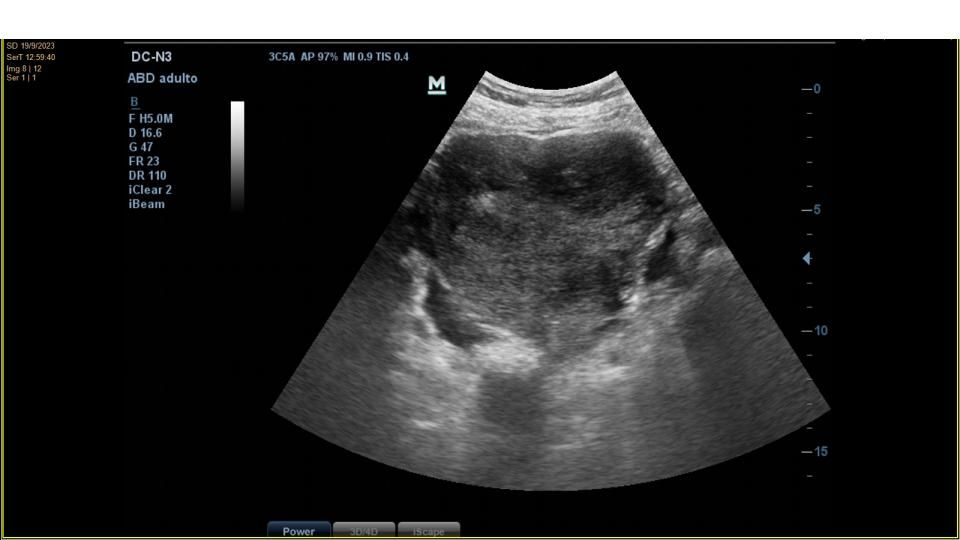

Se realiza ecografía clínica abdominal en el mismo acto para confirmar presencia de líquido y tratar de identificar la ocupación en flanco derecho.

La ecografía confirma la presencia de moderada cantidad de líquido libre abdominal y de una imagen de unos 10 cm de diámetro mayor, anecogénica, tabicada, que parece depender de ovario derecho.